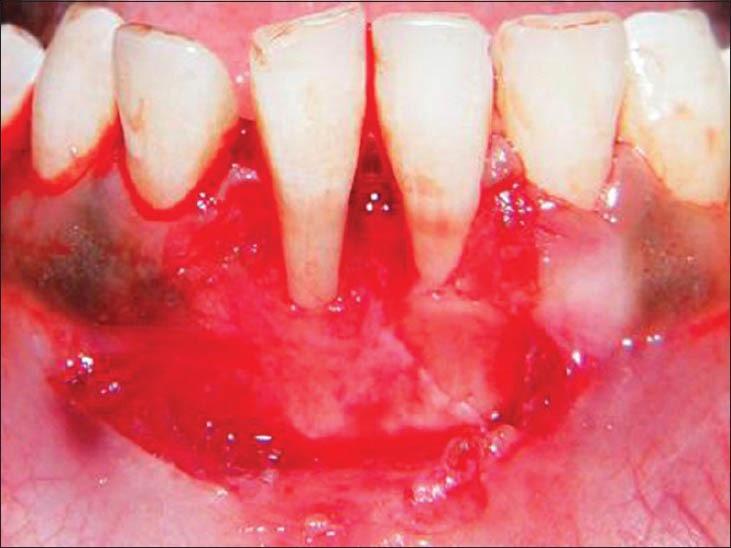

The purpose of this article is to limelight the benefit of periodontal microsurgery in the surgical disciplines. It reviews the benefits and potential applications of magnification and microsurgery in the specialty of periodontics and a case report on microsurgical approach for free gingival graft surgery in the treatment of gingival recession. The increased demand for mucogingival esthetics has required the optimization of periodontal procedures. Microsurgery is a minimally invasive technique that is performed with the surgical microscope and adapted instruments and suture materials. Although this hardware and knowledge of various operations are necessary to achieve patient esthetic expectations, clinicians must be willing to undergo an extended period of systematic training to become familiar with novel operating procedures and instruments. This article describes the application of the surgical microscope to provide enhanced perioplastic treatment.

本文的目的是突出牙周显微外科在外科领域的益处。它回顾了放大技术和显微外科在牙周病专科中的益处及潜在应用,并报告了一例采用显微外科方法进行游离龈瓣移植术治疗牙龈退缩的病例。对龈黏膜美学需求的增加要求优化牙周手术。显微外科是一种微创手术技术,通过手术显微镜以及适配的器械和缝合材料来实施。尽管要达到患者的美学期望,这些硬件以及各种手术知识是必要的,但临床医生必须愿意接受长时间的系统培训,以熟悉新的操作程序和器械。本文描述了手术显微镜在提供强化牙周成形治疗方面的应用。